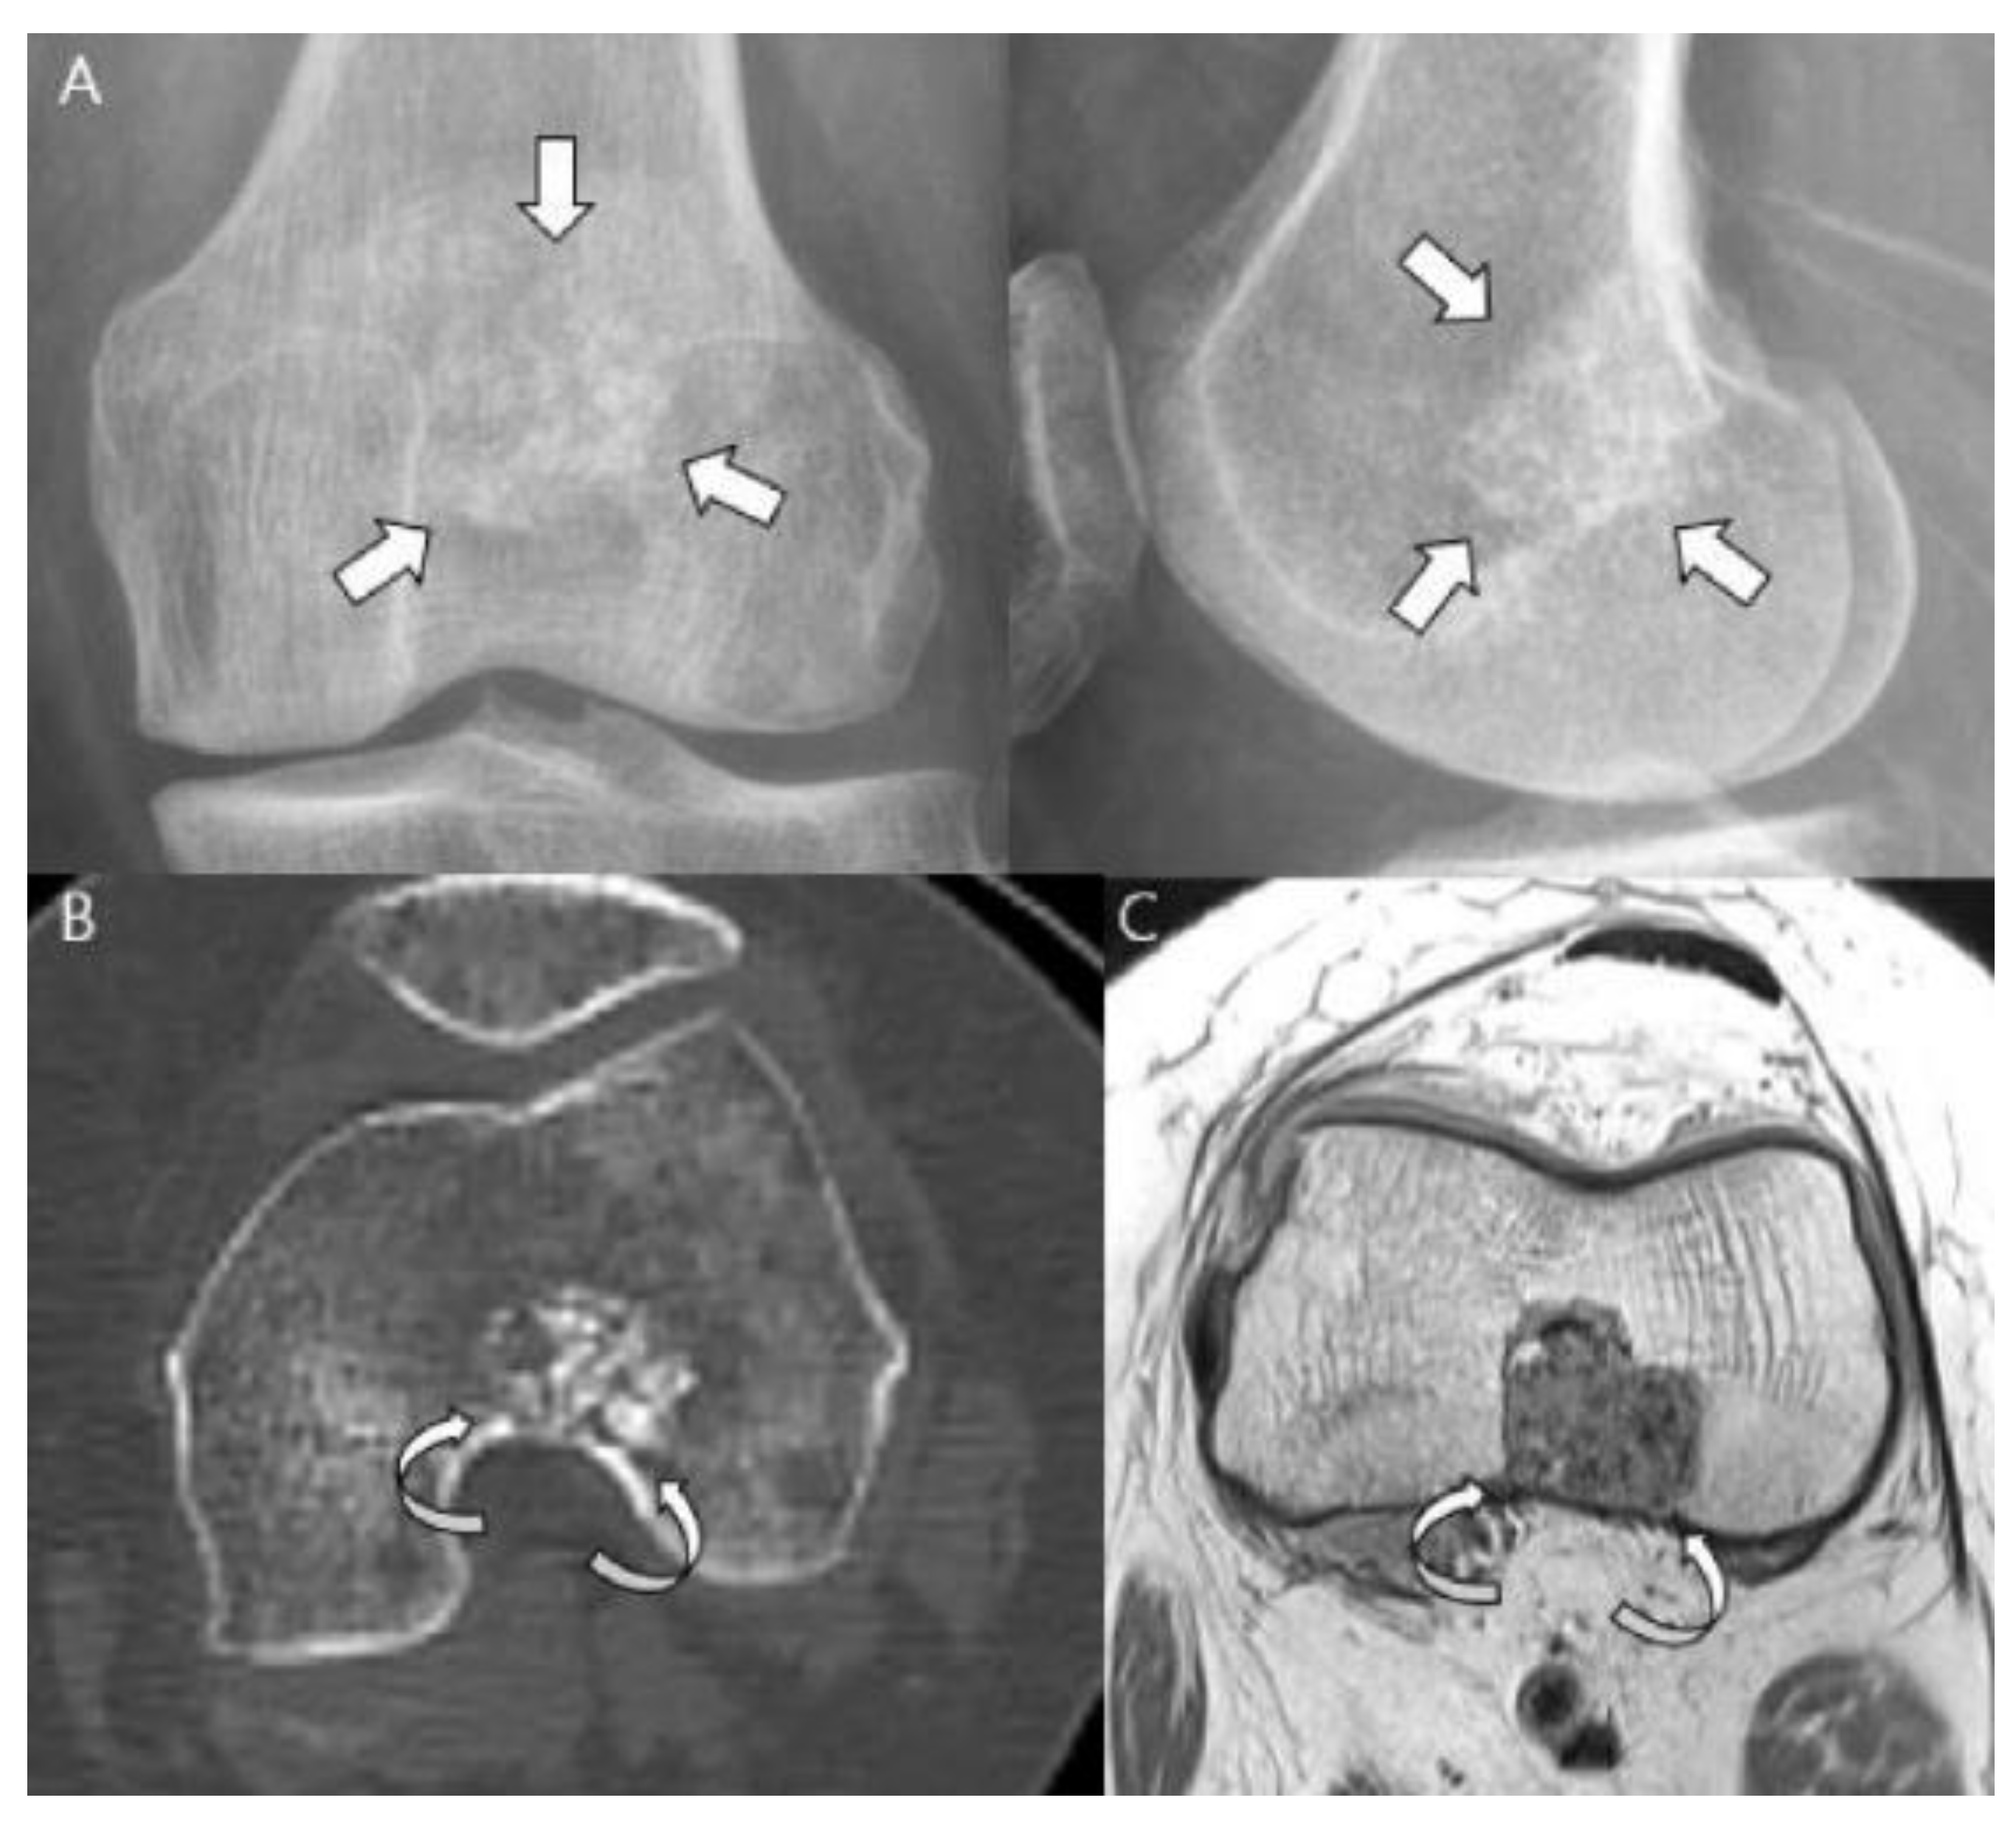

Sensitive radiographic features differentiating enchondromas from chondrosarcomas include deep endosteal scalloping ≥2/3 of the normal cortical thickness [5,15] (Figure 3). Extensive longitudinal endosteal scalloping over ≥2/3 of the lesion length is also strong evidence of chondrosarcoma (although a somewhat less reliable criterion) [1,24] (Figure 4).

Figure 3.

Atypical cartilaginous tumor of the distal femur in a 50-year-old woman. (A) Anteroposterior and lateral radiographs reveal a mixed lytic and sclerotic lesion in the distal femur (arrows) with typical ring-and-arc calcifications. (B) Computed tomography and (C) axial T2-weighted image demonstrate a lobulated chondroid tumor with deep endosteal scalloping (curved arrows) despite the small tumor size (1.7 cm).